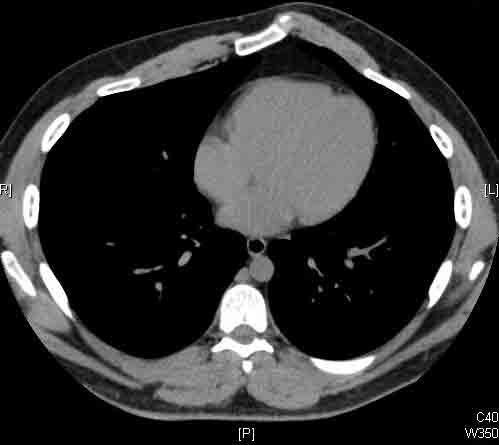

Here we present, as a paradigm of repair, the case of a 65 year old gentleman referred to our institution for an indolent mass in the left anterior chest wall. Repairs for other conditions follow the same rules. This mass had been stable in size for more than 12 months and the patient was prompted to seek medical attention as, after weight loss due to dieting, he felt the mass was uncomfortable while sleeping. Apart from coronary stenting for angina, the past medical history was unremarkable.

Computed tomography scan of the chest showed a mass protruding from the cortex of the third rib. A percutaneous core biopsy was non-diagnostic. We proceeded to an open incisional biopsy. This was reported as showing a spindle cell neoplasm. The patient was therefore scheduled, after multidisciplinary meeting discussion, for radical surgery.

At surgery, the mass was arising from the cortex of the third rib, and solid measuring 5x8 cm. There was no macroscopic involvement of the surrounding extra-thoracic musculature or of the underlying lung, the mass being confined to the rib and intercostal muscles. The patient underwent resection of the second to fourth ribs and the rhomboid muscle as well, in the attempt to get clear margin. The large antero-lateral defect was eventually reconstructed using 2 mouldable titanium bars. To prevent lung herniation through the defect, we reconstructed the layers anatomically using a biological patch (Veritas®). The final histopathology was a low grade sarcoma of the chest wall with clear resection margins.

He made an excellent recovery with daily physiotherapy to encourage shoulder movements. He was discharged with oral analgesia on postoperative day 4. At 1-month follow-up the patient had no pain at all, discontinued analgesia on postoperative day 17 and demonstrated a full range of shoulder movement. His chest x-ray was unremarkable and the wound healed without complication.